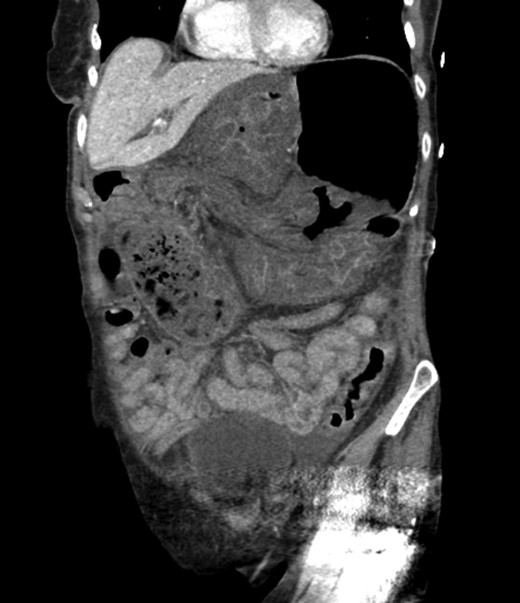

CT scan from four years prior to presentation showing evidence of foramen of Winslow hernia. Arrow head on stomach. Arrow on bowel.

Diagnosing an internal hernia is frequently accomplished using physical exam and CT imaging. Abdominal X-ray does have some nonspecific findings suggestive of internal hernia but is usually inadequate for diagnosis. Diagnosis of a foramen of Winslow hernia, however, is only accomplished in 10% of patients preoperatively [3]. As previously mentioned this diagnosis is rare and often presents with vague obstructive type symptoms. This likely contributes to the low occurrence of accurate preoperative diagnosis. However, several radiographic findings were seen in this patient that suggested a foramen of Winslow hernia preoperatively. First, there is visible swirling of the mesentery on the CT scan that is indicative of internal hernia (Fig. 1). Second, there are loops of small bowel that can be visualized between the IVC and the edge of the liver in a supra renal position along the lesser curvature of the stomach (Figs 1 and 2). When compared to a CT of the abdomen and pelvis obtained 4 years prior to presentation, there is actually evidence that this patient had a non-obstructing foramen of Winslow hernia at that time as demonstrated by bowel being visualized in the lesser sack (Fig. 5). These findings, especially small bowel along the lesser curvature of the stomach, are inconsistent with normal anatomy and strongly indicative a foramen of Winslow hernia.